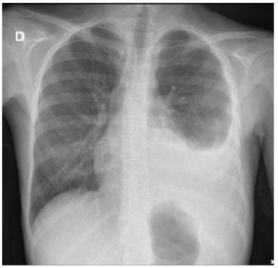

Paciente de 10 anos, feminino, previamente hígida, apresenta tosse e coriza há 7 dias e febre há 5 dias, prostração e dor abdominal há 2 dias. Nega trauma ou qualquer lesão ou infecção prévia ao quadro atual. Ao exame físico está em regular estado geral, pálida, com FC: 120 bpm, FR: 31 ipm, discreta tiragem de fúrcula sem outros sinais de desconforto respiratório. Ausculta cardíaca sem alterações, ausculta pulmonar com crepitações, diminuição de murmúrio vesicular e da ausculta da voz em base esquerda. Abdome flácido, levemente doloroso à palpação profunda. Oximetria de 95% em ar ambiente. Solicitado teste rápido para influenza A positivo. Hemograma e proteína C reativa (abaixo) e hemocultura (em andamento) e Raio X de tórax em pé e decúbito lateral esquerdo (abaixo).